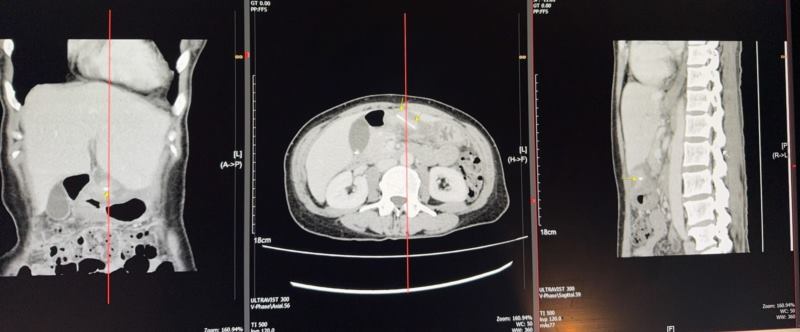

ตรวจร่างกาย กดเจ็บ epigastriun+RUQ จริง ด้วยความสงสัยจริงส่ง Ct เพิ่ม เห็นดังรูป Dx. Foreign body perforation ?? อะไรสักอย่าง Operation: EL+ remove. FB

สรุป ก้างปลาทะลุกระเพาะอาหาร ประสบการณ์เจอ เคสแรก ไม่มี free air. ไม่มี abscess มีwall. Off omentum+debies tissue เล็กน้อย (ลืมถ่าย intra op เพราะผ่าตี 3)